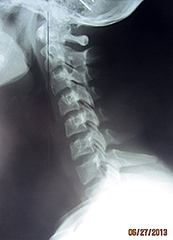

Fig. 3: Lateral Cervical (Normal)

Fig. 4: Lateral Cervical (Abnormal)

Figure 3 represents a normal cervical spine as seen from the lateral view. The lordotic curve provides shock absorption, the disc spaces appear to be full and the cervical gravity line, which is located by a point on the anterior third of the odontoid process then drawing a plumb line straight down, represents the center of gravity of the weight of the head (approximately 10% of body weight). In the optimal state, all bones in the neck should share in the distribution of this weight. In Figure 4, the head is grossly anterior to all of the bones in the cervical spine, the spine is straight and the loading of this neck is highly abnormal.